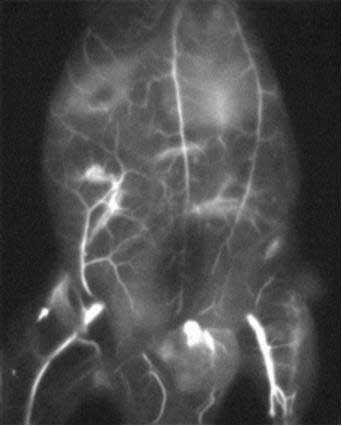

荧光成像:小鼠血管的可视化